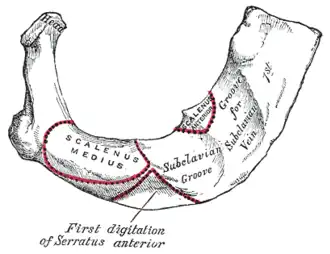

Première côte

La première côte est la plus large et la plus courte des côtes. Ses faces sont orientées vers le haut et vers le bas. Elle s'articule avec une seule vertèbre, la première vertèbre thoracique et avec le premier cartilage costal articulé à l'incisure costale du manubrium sternal formant la synchondrose sterno-costale de la première côte. Elle délimite latéralement dans un plan oblique en bas et en avant l'ouverture supérieure du thorax.

Sa face supérieure est marquée de reliefs qui lui sont spécifiques. Près du bord médial se trouve le tubercule du muscle scalène antérieur est un point d'origine du muscle scalène antérieur. Il sépare le sillon de l'artère subclavière en arrière du sillon de la veine subclavière en avant.

En avant du sillon de la veine, un tubercule permet l'insertion du ligament costo-claviculaire et du muscle subclavier.

En arrière du sillon de l'artère s'insèrent le muscle scalène moyen et le muscle dentelé antérieur.

Sur le bord latéral de la côte s'insèrent les muscles dentelé postérieur et supérieur et le premier muscle élévateur des côtes.